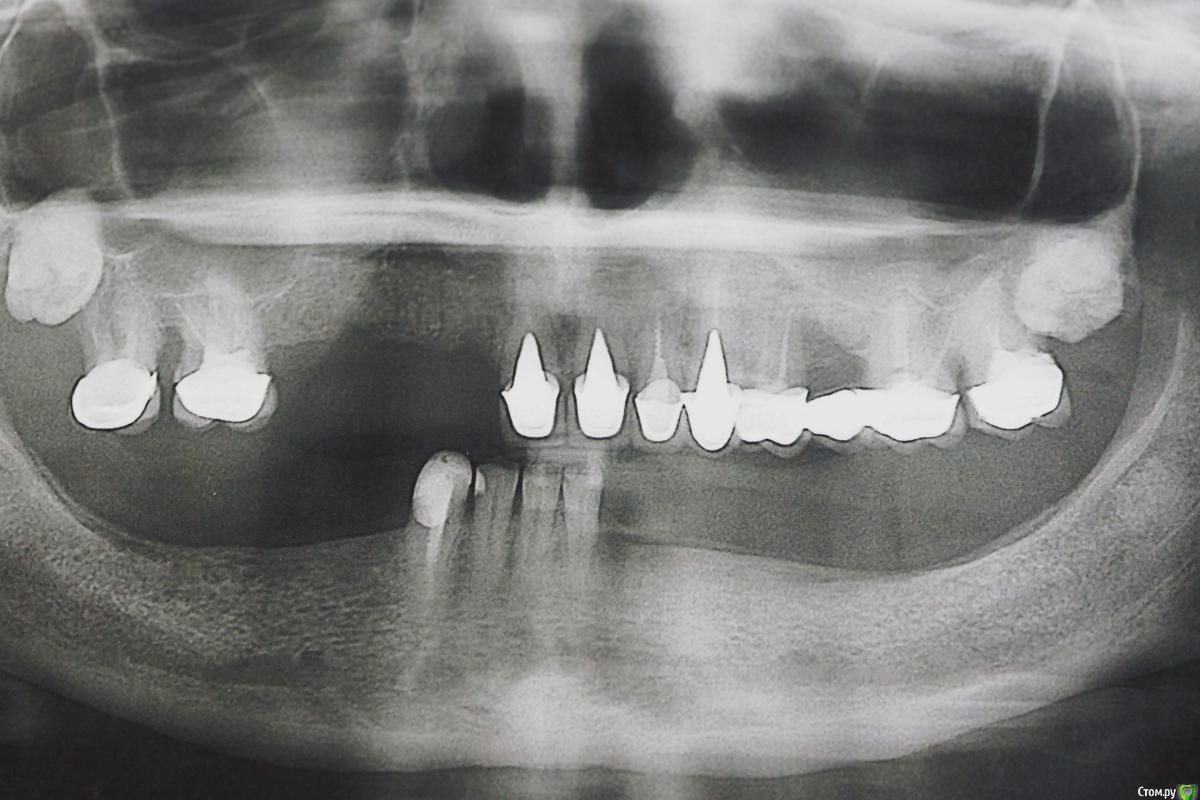

Dman Опубликовано 13 марта, 2019 Поделиться Опубликовано 13 марта, 2019 (изменено) Обратилась пациентка, панорама 2012 панорама 2018 Сейчас по ощущениям еще хуже Если с низом более или менее понятно, 4 винта и балка, чтобы разгрузить кость, то сверху вообще непонятно. Желание пациента жить и жевать. За эти 7 лет поменяли 7 съемных протезов, все они ей натирали и плохо держались. Анамнез чист, принимает только эстрогены Если есть кто-то из тольятти, кто готов взять пациента, с удовольствием передам контакты. Изменено 13 марта, 2019 пользователем Dman Ссылка на комментарий